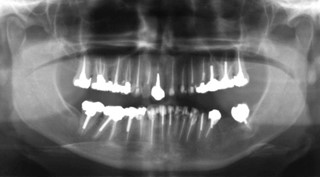

The dentoalveolar complex is a common source of orofacial pain, and most cases of acute dental pain are successfully diagnosed and treated by general dentists. However, toothaches can recur or persist despite treatments judged to be adequate (Figure 1), and deciding whether any subsequent tooth-related treatments can relieve the patient’s symptoms is not an easy task. Such a presentation should remind the dentist that the pain might not be “dental” in nature even though the patient may point to a tooth.1 Lack of certainty about the absence of a dental cause of pain (for example, a possible cracked tooth or adjacent offending tooth) or the possibility of failed tooth-related treatment, despite a thorough history and diagnostic procedures, is often responsible for unnecessary or inappropriate dental treatment. This article presents a clinical reasoning process for improving the diagnostic and treatment approach for dentists managing patients with recurrent and persistent dental pain.

Figure 1: Panoramic image of the dentition of a 42-year-old female patient referred to an oral medicine specialist with multiple complaints, including pain in all her teeth.